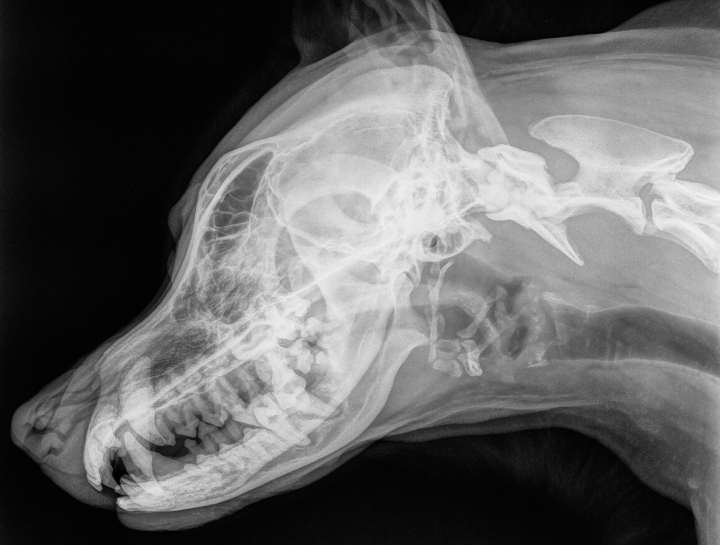

Digital Dental Radiology

Insight into underlying issues.